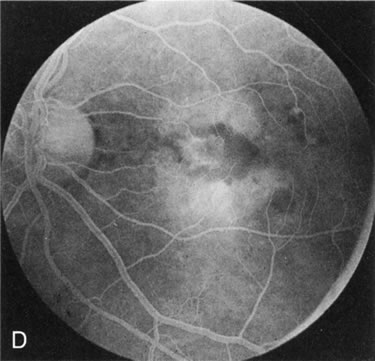

In Stargardt's disease, thes most common hereditary macular dystrophy, FA has a variety of functions. In the mildest fundus presentation, with visual symptoms and visual function out of proportion to the observed maculopathy, FA can confirm or even make the diagnosis and can avoid a mistaken diagnosis of malingering, hysteria, or central nervous system disease (Fig. 9A and B). When a maculopathy is present without surrounding parafoval flecks, FA may show patchy areas of transmission hyperfluorescence in the posterior pole, indicating a more diffuse involvement (Fig. 9C and D).

Fig. 9. Stargardt's disease–fundus flavimaculatus. The mild maculopathy (without parafoveal flecks) (A) is confirmed by the angiogram (B). The relative absence of the underlying choroidal flush, resulting in an easier visualization of the overlying retinal capillary circulation, has been referred to as the “silent” or “dark” choroid, and is considered a common finding in this disease. The diagnosis is confirmed in an individual with a pigmentary maculopathy without flecks (C). Here the angiogram demonstrates widespread transmission hyperfluorescence and a “silent” or “dark” peripapillary area (D). When the posterior pole shows multiple yellowish-white flecks (E), the angiographic findings do not necessarily correspond to the flecks (F). It should also be noted that despite the widespread abnormalities, the background choroidal fluorescence is normal.

In a large majority of patients (86% in one study),20 there is an absence or decrease in the background choroidal fluorescence (which is referred to as the “silent” or “dark” choroid) (see Fig. 9B). This warrants special attention because it occurs so frequently, is rarely found in other retinal disorders,21 and may be related to histopathology that shows an increase in lipofuscin in the RPE.22